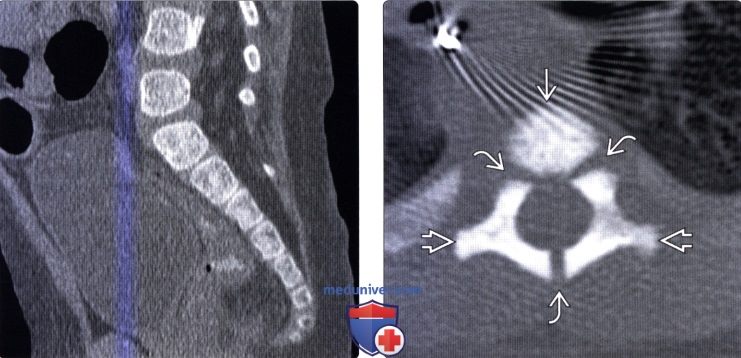

Рентгеновские снимки крестцово-копчикового отдела позвоночника